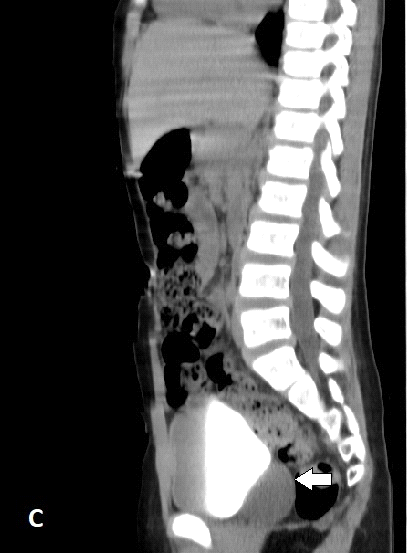

Se le realiza ecografía en la que se observó en proyección de hipogastrio imagen ecolúcida, redondeada, de paredes bien definidas, regulares de 32 x 29 mm en contacto con la pared posterior hacia el lado izquierdo que impresiona quiste de vesícula seminal. La tomografía axial computarizada demostró la ausencia de la unidad renal derecha por nefrectomía anterior, se evidencia imagen hipodensa, de paredes bien definidas, redondeada hacia la pared posterior izquierda de la vejiga (Figura 1) que no realza con el uso del contraste, en relación a quiste a nivel de la vesícula seminal izquierda que oscila entre 5-13UH (Figura 2 y 3). Se decidió como conducta terapéutica punción y drenaje por aspiración de la lesión. Se mantiene en seguimiento, hasta la fecha no se evidencia recidiva.

Fig. 2. Tomografía contrastada corte coronal donde se observa la imagen hipodensa que no realza con el contraste utilizado.

Fig. 3. Tomografía contrastada corte sagital donde se observa la imagen antes descrita en cara posterior de la vejiga.